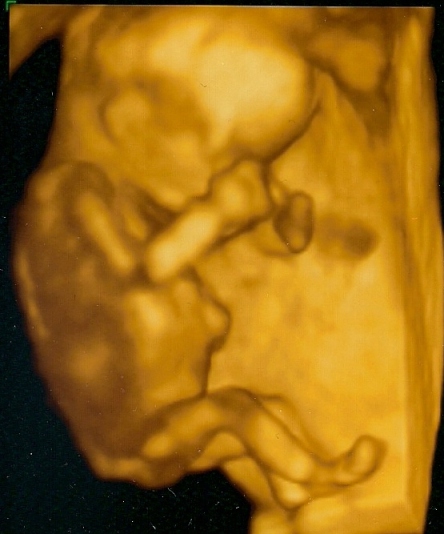

Újabb pasi érkezik Kolos. :D

16 hetesen ilyen. :wink: